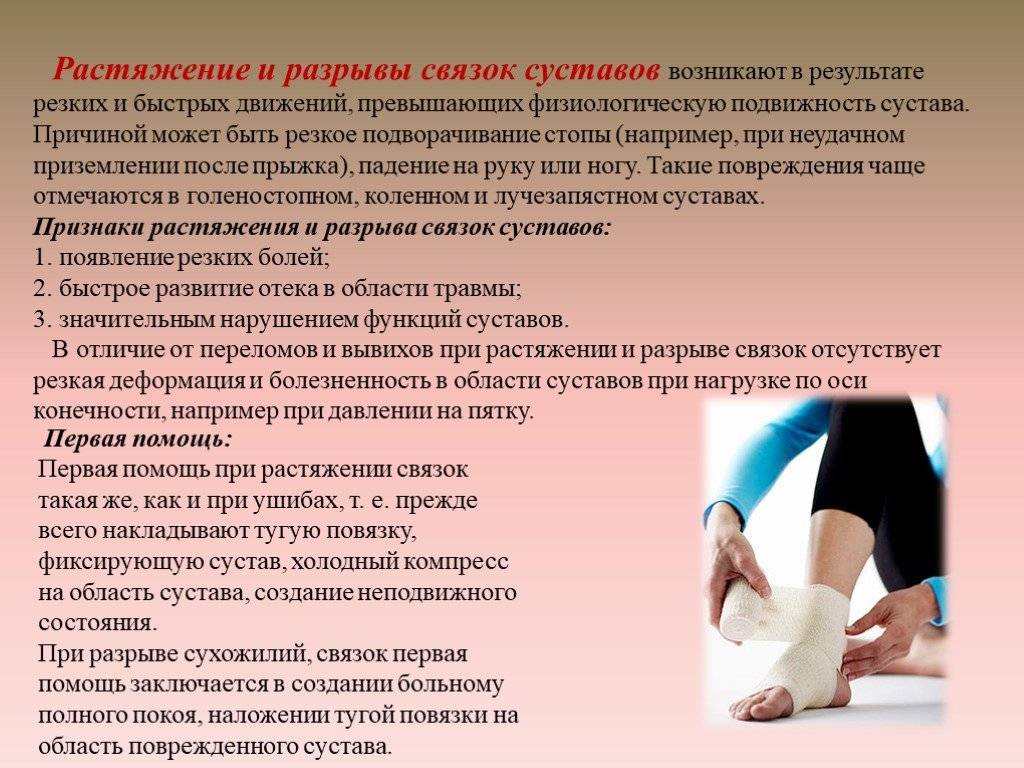

Причины и лечение травм коленного сустава